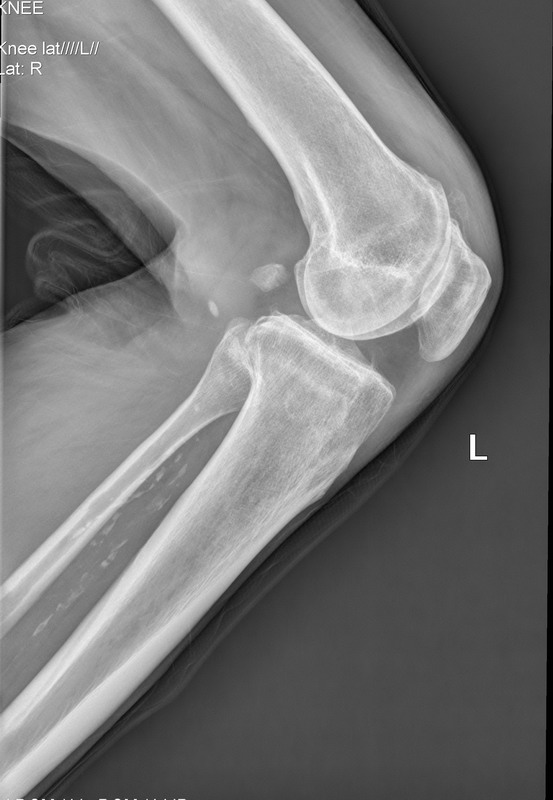

以下是引用随光逐影在2010-4-12 8:14:00的发言:[br]1)双膝关节退行性改变。2)双小腿软组织内钙化(骨间膜钙化?血管壁钙化?)。